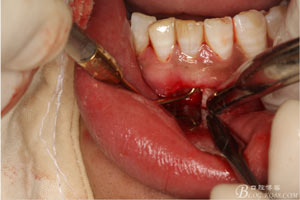

圖9.清晰可見(jiàn)牙膠從31根尖1/3溢出。